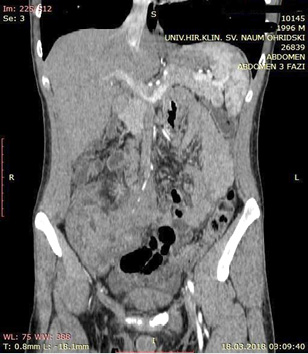

A contrast enhanced CT scan was indicated due to the palpable abdominal tumor and it revealed a formation that originates from the ileal mesentery involving the ileocolic artery and a part of the ileum with ileal wall thickening and partial obstruction (Figures 2, 3 and 4).